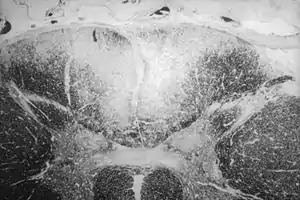

Secção axial da medula espinhal mostrando a destruição causada pela sífilis (área esbranquiçada, no região central superior) das colunas posteriores, que carregam informação sensorial do corpo em direção ao cérebro

Tabes dorsal é uma lenta degeneração de neurônios que carregam informação sensorial para o cérebro. Os nervos que se degeneram nesta doença estão localizados nas colunas dorsais da medula espinhal e carregam informações que ajudam a pessoa a manter seu senso de posição (propriocepção), senso de vibração e toque fino (sensibilidade epicrítica).